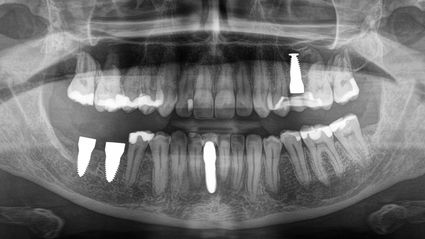

Ich besuchte die SWISS BIOHEALTH CLINIC im März 2019, nachdem ich alles über ihren ganzheitlichen biologischen Ansatz in der Zahnmedizin für Metallimplantate gelesen hatte, und wusste, dass dies ein neuer Schritt auf meinem Weg zur Gesundheit war. Unmittelbar nach der Entfernung des Titanimplantats begann sich mein Körper zu entspannen, die anhaltenden Schmerzen in meinem linken Ellbogen verschwanden und meine Sehkraft auf dem linken Auge kehrte zurück.